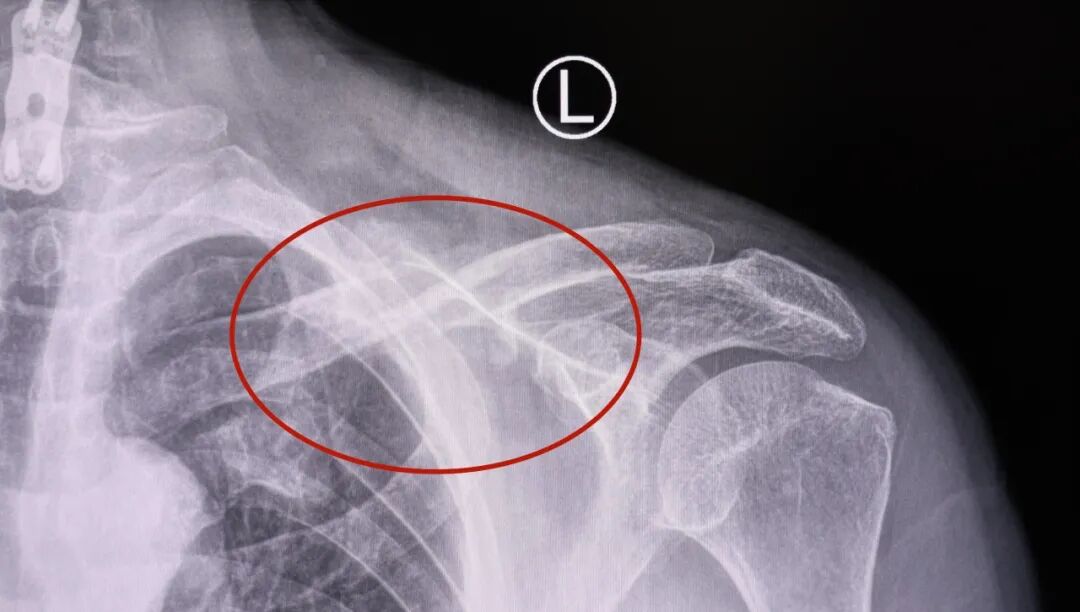

一个月前,67岁的张大爷不小心摔了一跤,左边肩膀当时就疼了起来,但又觉得还能扛得住,就没去医院。没过多久,张大爷突然出现了轻微偏瘫,家人赶紧把他送到西安高新医院检查。拍完片子后,医生竟发现他左边的锁骨断了,建议进行骨科手术。但当时张大爷因为脑梗,在吃抗凝血药,做手术容易出现出血,风险比较大,自己又觉得骨折能慢慢长好,就没当回事。

就这样拖了一个月左右,张大爷感觉左肩膀越来越沉,接着左胳膊前臂肿了起来,左手也开始发麻,就算歇着也不见好。直到手麻得越来越厉害,他才赶紧到西安高新医院骨科一病区就诊。医生检查后发现他左边锁骨断的地方已经错开了,胳膊肿得明显,手感觉也变迟钝了,碰一下还疼得厉害,明显是断裂的锁骨把神经和血管被压到了,张大爷这才意识到问题的严重性,于是住院接受治疗。